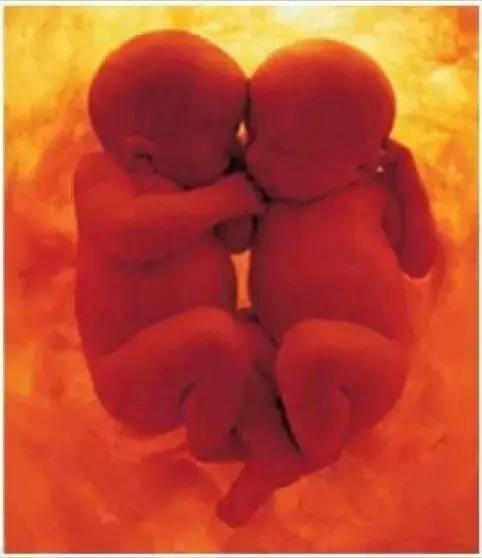

随着医学技术的进步,现在通过仪器就可以看到宝宝在准妈妈肚子里的状态,但你绝对想不到下面这些令人难以置信的照片竟展示了一对双胞胎在子宫内打闹和交谈。简直惊呆了!

请看下面的动图,真是太萌了